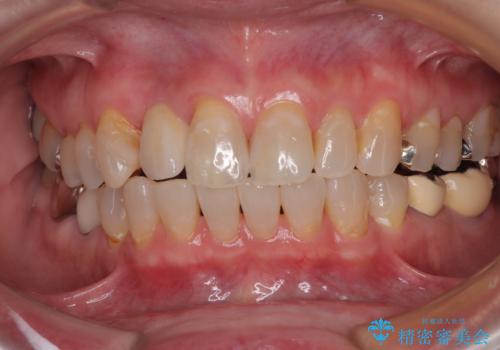

新幹線や飛行機を利用しても来院であり、極力来院回数を減らしたり、東京に用事があるタイミングに合わせてアポイントを調整したりと、負担が少なくなるようにして治療を進めて行きました。

来院間隔があいたため、予定よりも長くなりましたが、大きなトラブルもなく、外科処置は1回のみ、最小の来院数で無事に治療を終えることができました。